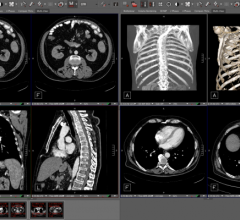

eHealth Saskatchewan plays a vital role in providing IT services to patients, health care providers, and partners such ...